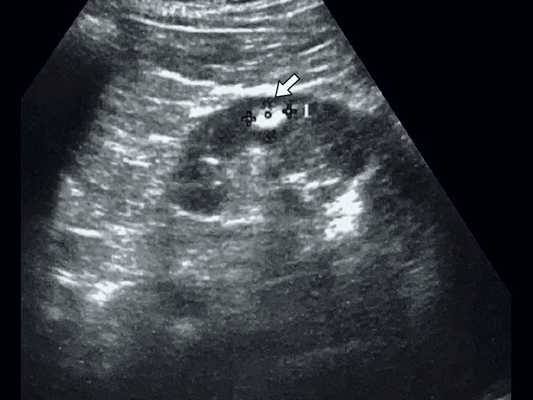

3. УЗИ при абсцессе почки:

• Исследование в режиме серой шкалы:

о Анэхогенное или гипоэхогенное скопление жидкости, сливающееся с нормальной эхогенной жировой клетчаткой в пределах фасции Героты

о Образование в почке или смещение почки

о Округлое комплексное образование с тонкими или гладкими стенками

о Возможны внутренние перегородки или камеры

о Низкоуровневые внутренние эхо-сигналы (внутренний детрит)

о «Кольцевидные» артефакты, «грубая акустическая тень»

• Цветовая допплерография:

о Поток на периферии (гиперемия)

о Отсутствие потока в центре или только в перегородке

(Справа) УЗИ правой почки в сагиттальной плоскости: у того же пациента выявлено округлое анэхогенное образование с низкоуровневыми внутренними эхо-сигналами и задним акустическим усилением. Лихорадка в анамнезе и данные визуализации указывают на наличие абсцесса.

На ультразвуковом изображении визуализируется гипоэхогенный очаг с гиперэхогенным включением, что соответствует на жидкостное включение.

Диагноз — абсцесс.